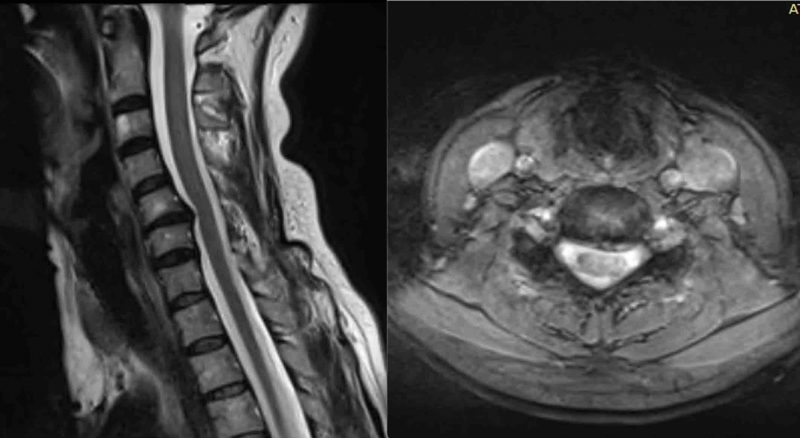

Paciente varón 45 años, operado hace 2 años artrodesis C6-C7. Acude por presentar dolor cervical y persistencia de hormigueo y acorchamiento en miembro superior izquierdo, sobre todo en segundo y tercer dedos. El acorchamiento no desapareció tras la primera cirugía. Se solicita una resonancia magnética de columna cervical y un electromiograma.

RMN Columna Cervical: Cambios postquirúrgicos con material de fijación. Hernia discal C5-C6.

Hernia discal C5-C6, material de fijación C6-C7

Electromiograma: Cambios denervatorios crónicos en miotoma C7 izquierdo

Paciente presenta síndrome de nivel adyacente, es decir el disco inmediato superior a la cirugía previa se lesiona produciéndose la hernia discal. Tras las pruebas se decide reintervenir al paciente. En este caso consideramos que la artrodesis percutánea de columna cervical con D-TRAX es la mejor opción quirúrgica. Al abordar el problema por vía posterior evitamos la fibrosis de la primera cirugía. También evitamos la posibilidad de lesionar estructuras nerviosas importantes. Además la recuperación del paciente será más rápida.